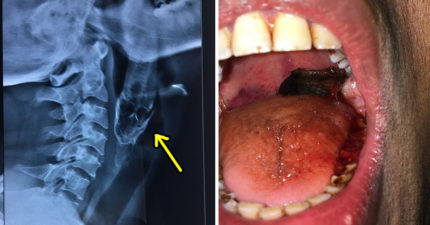

男子「活魚卡喉嚨」痛苦快死,醫生「拉出整條畫面」大傻眼!